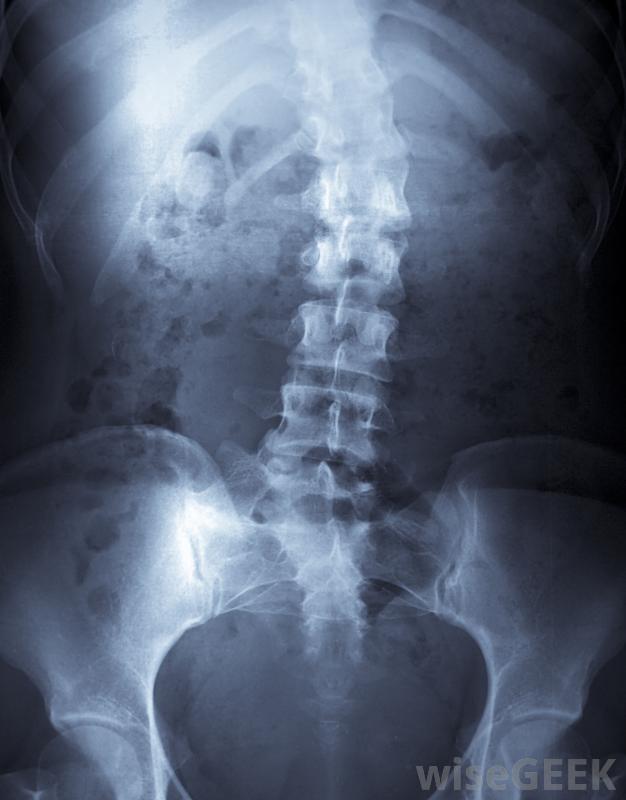

脊柱闭合不全的人可能有患脊柱侧凸的风险。脊柱闭合不全也可能是一个更微妙的问题,神经管几乎完全闭合,而内部结构却不能隐性脊柱裂是闭合性脊柱闭合不全最常见的一种形式,它可能会或不会引起身体症状和健康并发症。大多数先天性隐性脊柱裂的儿童尽管有一些小缺陷,但发育正常,不需要特殊治疗。偶尔,下脊柱可能有一个凹痕,容易导致毛发过度生长。患者可能在以后的生活中面临并发症的风险,如脊柱侧凸、弯曲或扭转困难,以及椎间盘突出,需要手术治疗